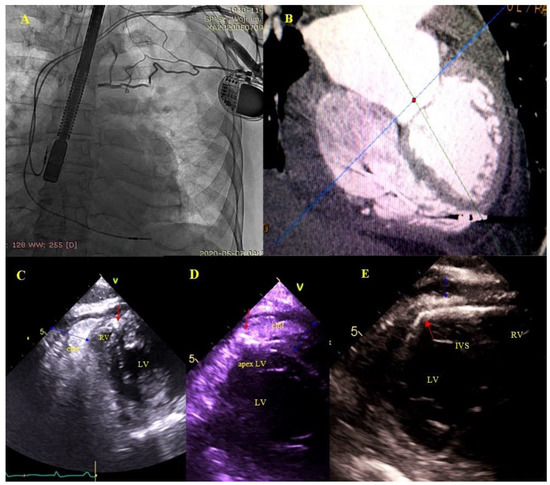

2.5. Echocardiographic Findings Associated with Endocardial Leads: Definition and Classification According to the Anatomy and Characteristic Features